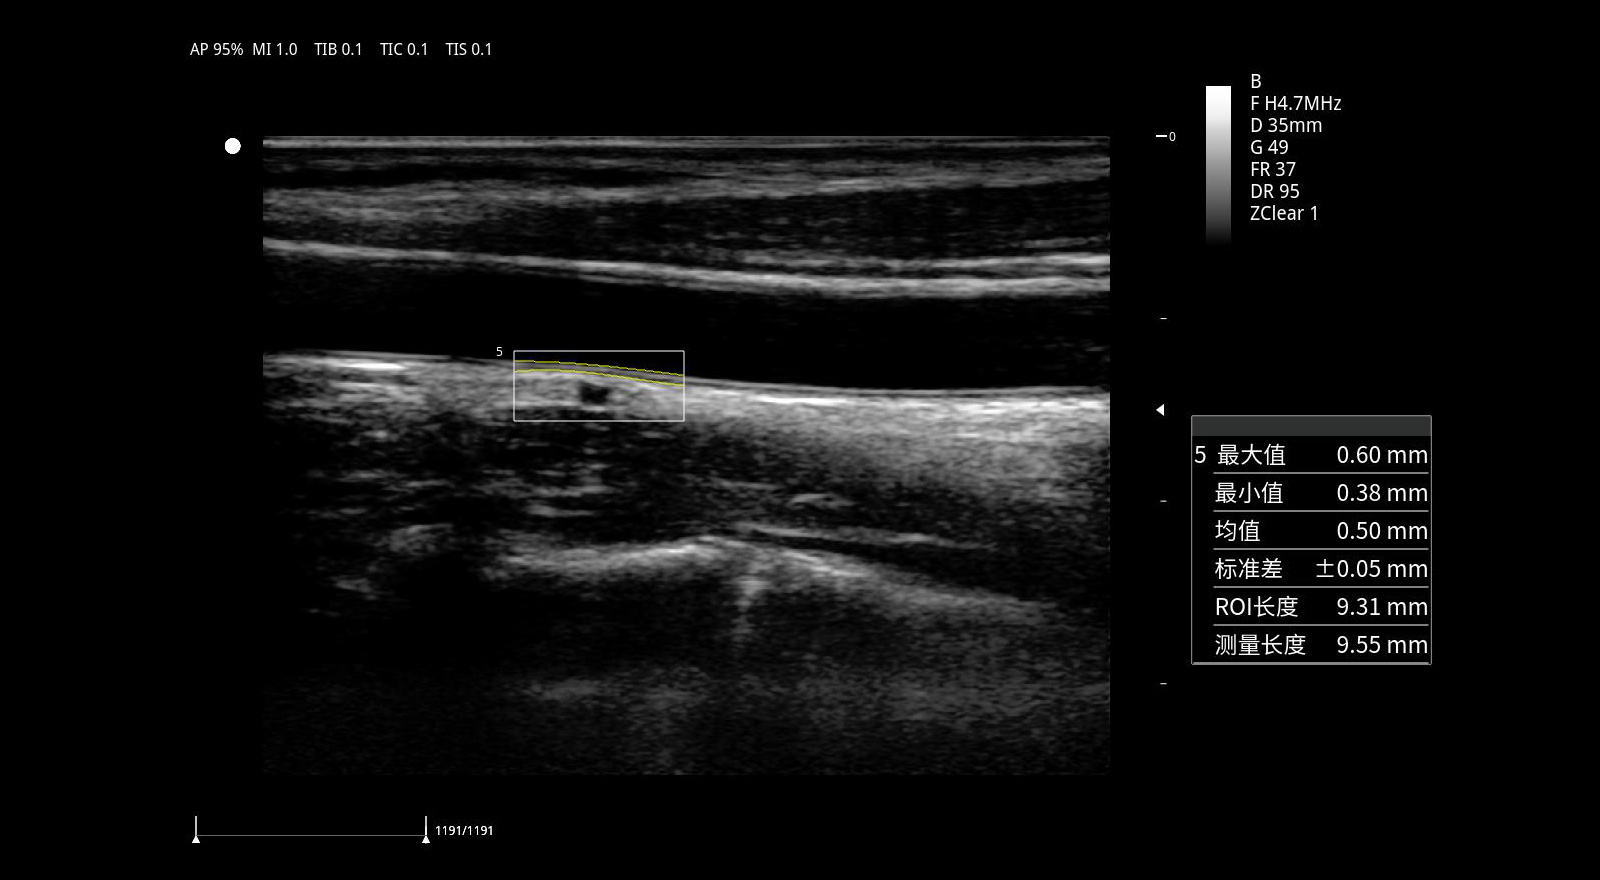

Medición automática del espesor íntima-media. IMT.

Con IMT, se puede detectar y medir automáticamente el espesor de la íntima-media y se puede generar un informe de espesor de la íntima-media, lo que proporciona predictores independientes para la prevención de eventos cardiovasculares.

Medición automática del espesor íntima-media (IMT): Detección y medición automática del IMT con informe completo, útil en prevención cardiovascular.

Optimización en estudios cardiovasculares mediante medición automática de IMT.